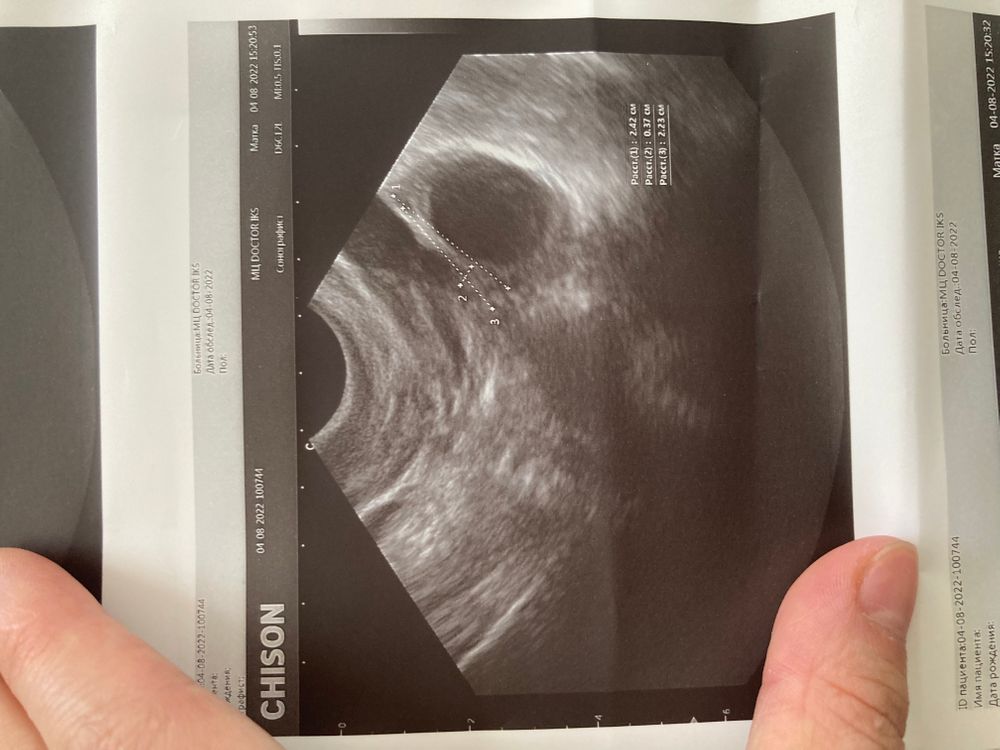

Что это?узи фолликулометрия

Доминантный фолликул ?Желтое. Тело?или Киста ?есть малое количество жидкости позади матки еще(незначительное)

Это фолликул. Какой размер намерили? Это точно не Желтое тело тк желтое тело с перегородками

Ну пока просто нелопнувший фолликул , будет размером ближе к 30 и без перспективы к овуляции то будет киста , на жт не похоже